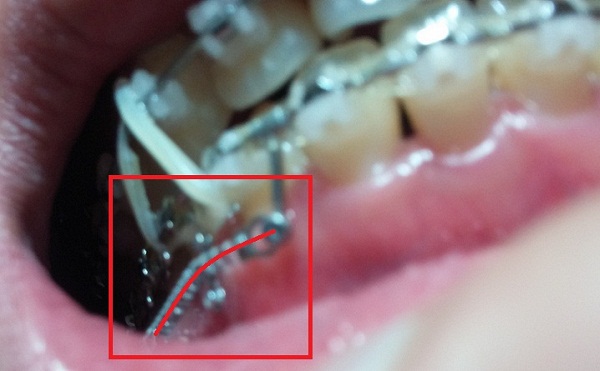

[스프링 정면]

[스프링 옆면]

+스프링사이에 또 다른 쇠기둥 보이시죠?! 저건 스프링이 잇몸에 닿아서 짓눌리지 않게 하기 위해서 해둔 조치랍니다.(제가 눌려서 아프다고 호소했더니 저런 방법으로 해주셨어용^^)

[스프링아래서 본]